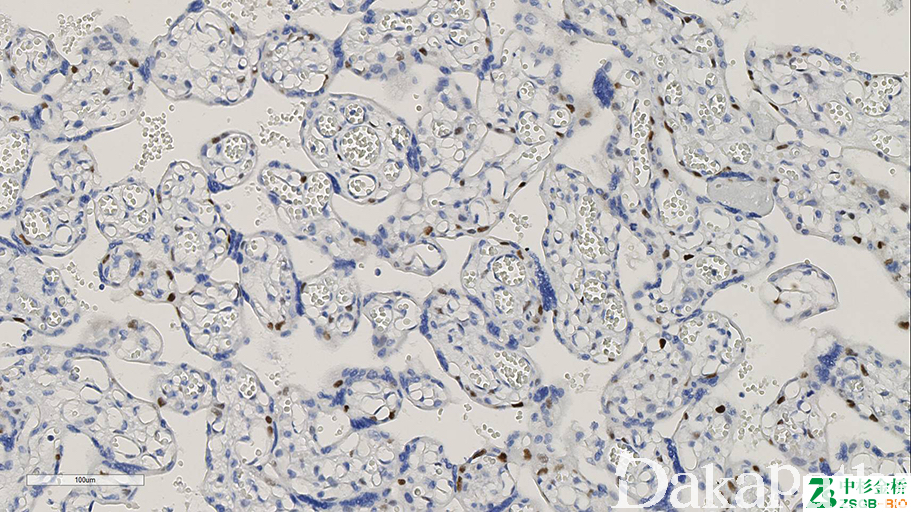

是一种细胞周期素依赖的激酶抑制剂和抑癌基因。蜕膜细胞阳性;正常胎盘细胞滋养叶细胞、中间型滋养叶细胞及绒毛间质细胞阳性;完全性葡萄胎时,细胞滋养叶细胞和绒毛间质细胞阴性。

信号定位: 胞核

完全性水泡状胎块(阴性)与部分性水泡状胎块及绒毛水肿的鉴别诊断。

几乎全部阳性(≥95%的病例阳性): 部分性水泡状胎块

几乎全部阴性(<5%的病例阳性): 完全性水泡状胎块